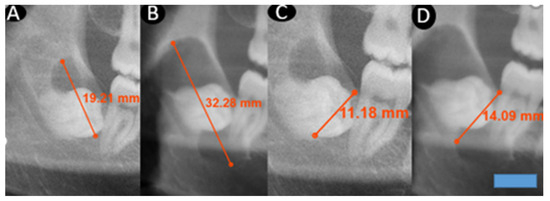

Background and Objectives: Dentigerous cysts are benign odontogenic lesions associated with the crowns of impacted teeth and are the second most common odontogenic cyst after radicular cysts. Despite being described as slow-growing, their growth has not been numerically quantified. This study aims to determine the radiological growth rate of dentigerous cysts through quantitative analysis, to clarify their biological behavior, improve clinical management, and guide future research by filling a significant gap in the literature. Materials and Methods: In this retrospective study, records of 187 patients diagnosed with dentigerous cysts at Dicle University between 2020 and 2024 were reviewed. Twelve patients with cysts associated with mandibular impacted third molars and at least two high-quality panoramic radiographs taken at different time points were included. In all of these patients with adequate and suitable radiographic records, the dentigerous cysts were associated with mandibular third molars, which contributed to the standardization of imaging and measurements. All images were obtained using the same digital system and converted to DICOM format. Maximum anteroposterior (A–P) and inferosuperior (I–S) dimensions were measured twice by the same examiner, and mean values were recorded. Follow-up intervals were noted, and monthly dimensional changes were evaluated. Due to the rarity of untreated cases, a sample of only 12 patients was considered meaningful. Results: Most patients were female, with no significant gender differences in age or follow-up time. Cyst dimensions increased over time, showing marked enlargement in the anteroposterior (A–P) direction and a similar upward trend in the inferosuperior (I–S) dimension. Conclusions: In our study, growth in the anteroposterior direction was higher than that in the inferosuperior direction, and no significant differences in growth rates were observed with respect to sex or age. Full article

(This article belongs to the Section Dentistry and Oral Health)

Show Figures

Figure 1